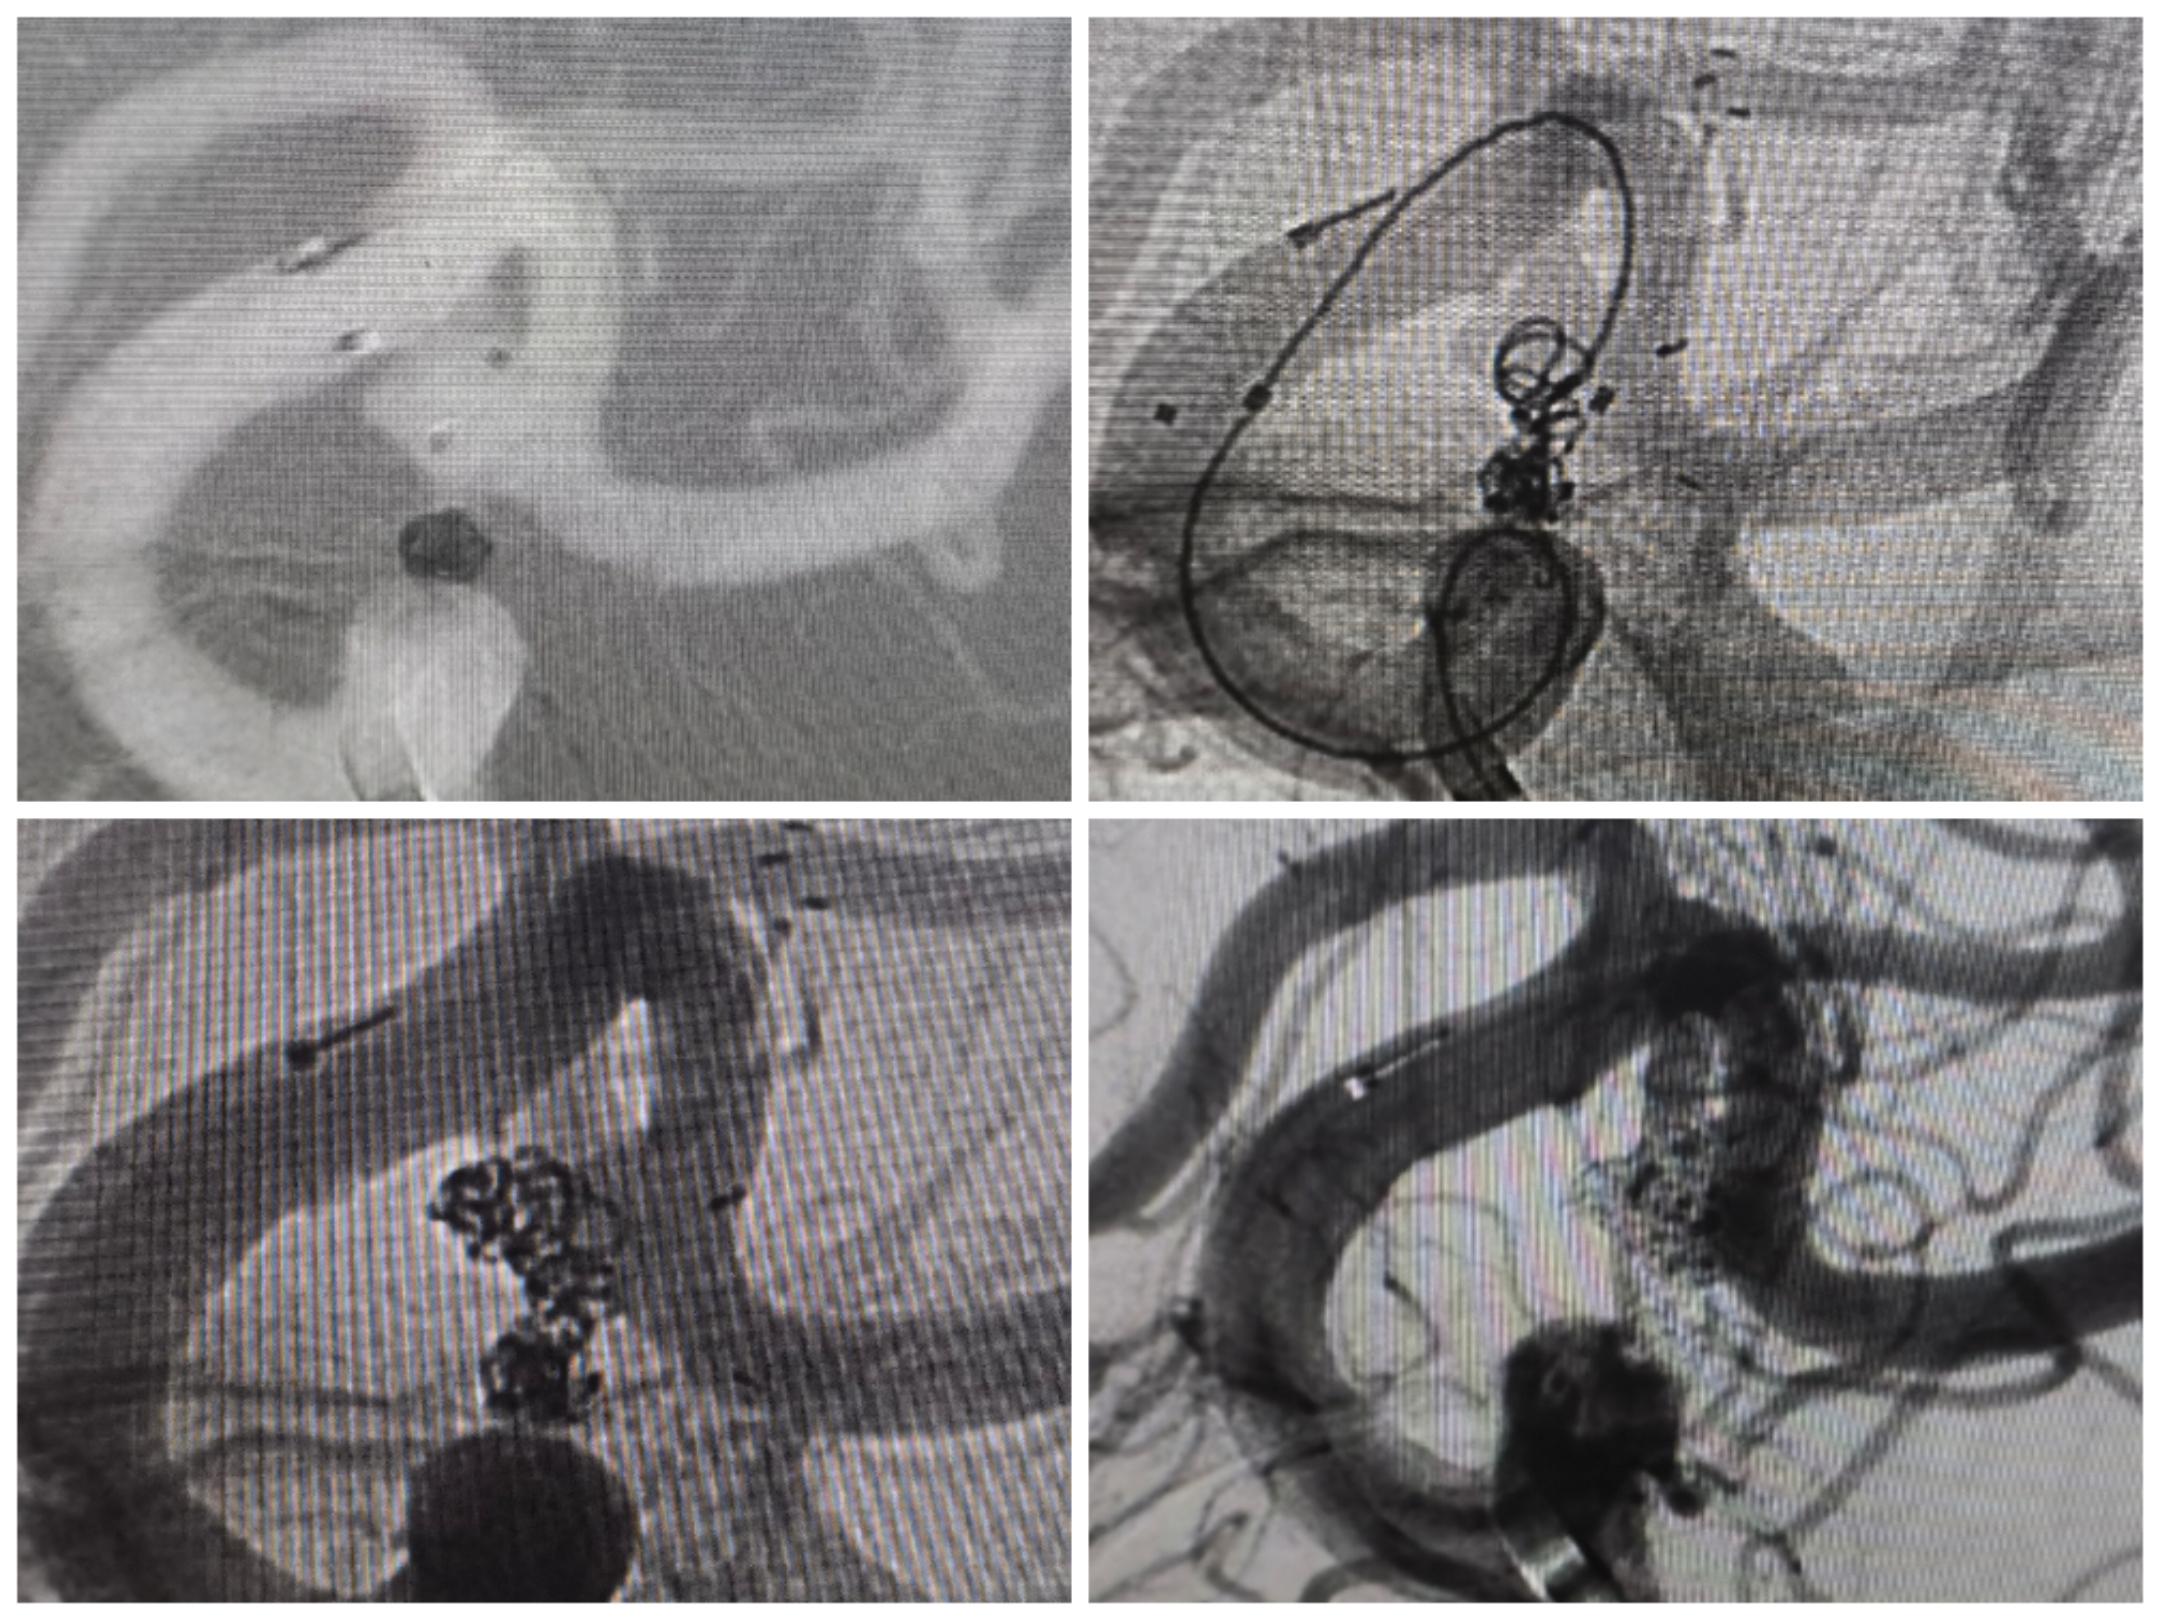

病例4后交通动脉瘤

患者因右侧眼睑下垂、动眼神经麻痹入院,CT无出血。

右侧颈内造影提示后交通不规则动脉瘤

椎动脉造影提示右侧P1良好,无需刻意保留后交通动脉

3D重建情况

拟支架辅助+双微管栓塞,微导管布局情况

先栓塞远端子囊+支架释放,双微管交替栓塞

栓塞术后情况